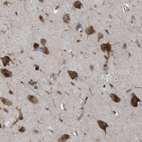

Immunohistochemistry analysis in human cerebral cortex and duodenum tissues using HPA017438 antibody. Corresponding GPRASP2 RNA-seq data are presented for the same tissues.